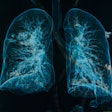

Characteristic pediatric lung findings are emerging

AI helps distinguish COVID-19 from other pneumonias